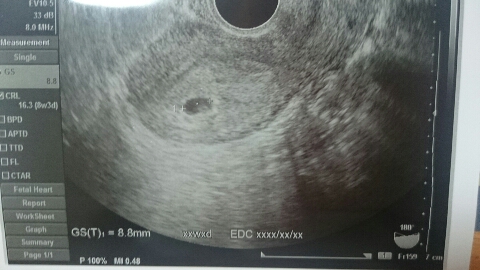

JUGEMテーマ:妊娠中のできごと 7週目にして小さい胎嚢しか確認できず、毎日不安のなかつわりの症状が出始めて赤ちゃんが成長しているんだと信じて毎日子宝授かりのお守りを枕元に置いた。神棚の前でお願いもして、とにかく念じていた(笑) 毎日基礎体温をはかりつづけて、下がっていないことを確認してホッとする朝の繰り返し。 そして二週間の検診の日、夫と病院へ。 赤ちゃんが成長していることがわかりました。うれしくてまた涙がうるっとして先...

JUGEMテーマ:妊娠中のできごと 土日に検査薬でうすい陽性反応が出て 5月23日がたまたま仕事の休みだったので、早速産婦人科へ。 でもその時は検査薬と同じように薄い反応だったようで、残念ながらまた日にちおいて来るようにとのこと。 妊娠初期上症状は出始めていて、妊娠している!という実感はでてきた。勝手に(笑) ただ、無事に成長するのかな、大丈夫だろうかと不安でいっぱい。 最初は6月3日に予約。一週間以上あいているし、排卵日からの計算では7週になるから心拍確認も出来る!と...